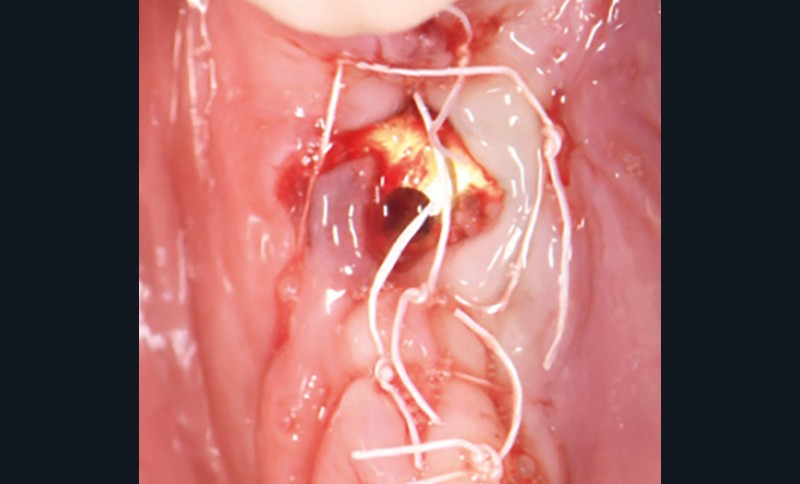

La couronne a été déposée et une vis de couverture mise en place. La patiente a reçu un nettoyage supra-gingival général avec une attention particulière pour l’implant 47, et une irrigation locale avec du gel de chlorhexidine et du peroxyde d’hydrogène pour réduire l’inflammation des tissus. De l’amoxicilline (3 x 500 mg) a été prescrite, à commencer la veille de l’intervention chirurgicale.

La patiente est restée 4 semaines sans couronne. Après l’intervention chirurgicale, elle a entamé un programme de soins péri-implantaires et parodontaux, avec des visites de rappel tous les 4 mois.